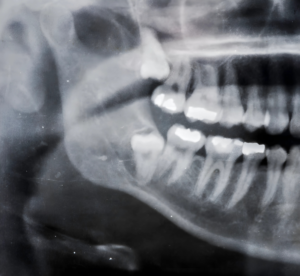

Radiografia panorâmica da arcada dentária, mostrando dentes, raízes e estruturas ósseas da mandíbula e maxila.

Protocolos de Emergência e Cuidados Pós-Exodontia

Os protocolos a serem seguidos durante o atendimento de pacientes com necessidade de exodontia envolvem não apenas a extração em si, mas também a avaliação do estado geral de saúde do paciente. Após a exodontia, orientações sobre cuidados pós-operatórios, como controle da dor e prevenção de infecções, são essenciais. O seguimento do paciente, realizando visitas subsequentes para verificar a cicatrização e o alívio da dor, contribui para um atendimento de qualidade em odontologia de urgência e emergência.